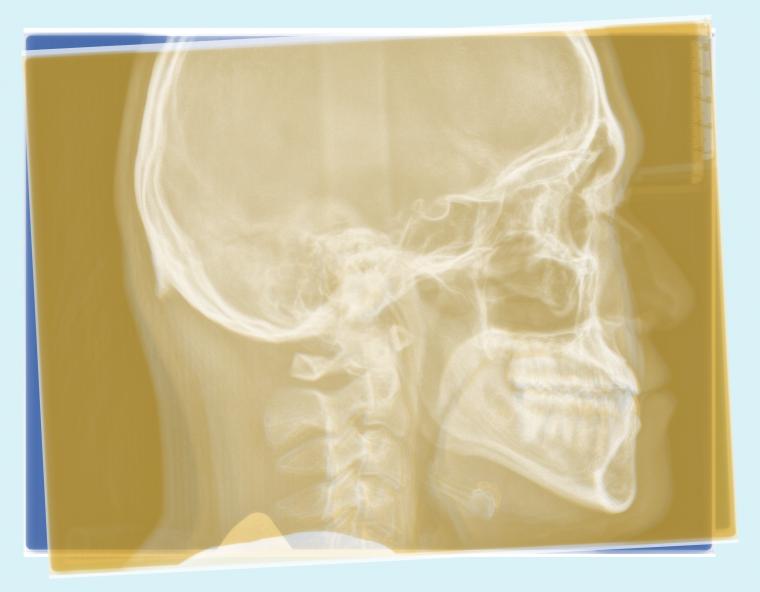

#46 下顎歯列の後方移動を行った症例